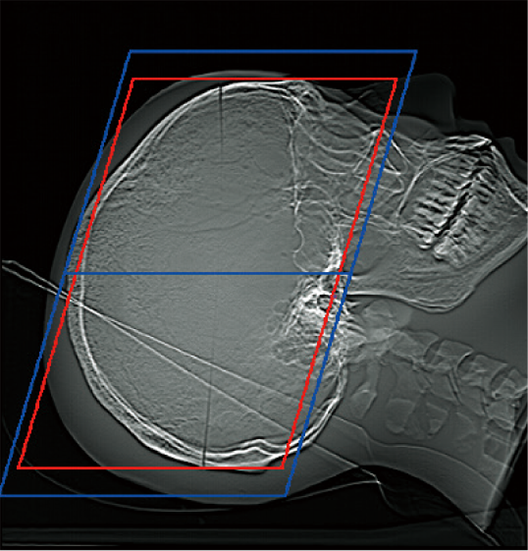

透過掃描定位圖影像,即可自動設定掃描範圍,有助於提升掃描位置的再現性與檢查效率,進而縮短整體檢查時間。

掃描範圍的邊界可依各醫療機構的作業習慣預先設定,實現符合需求的自訂化操作。操作者亦可隨時檢視與調整自動計算出的掃描範圍。*4

OM Line

SM Line

RB Line

Chest

紅色:自動設定位置

藍色:自動設定位置 + 設定邊界